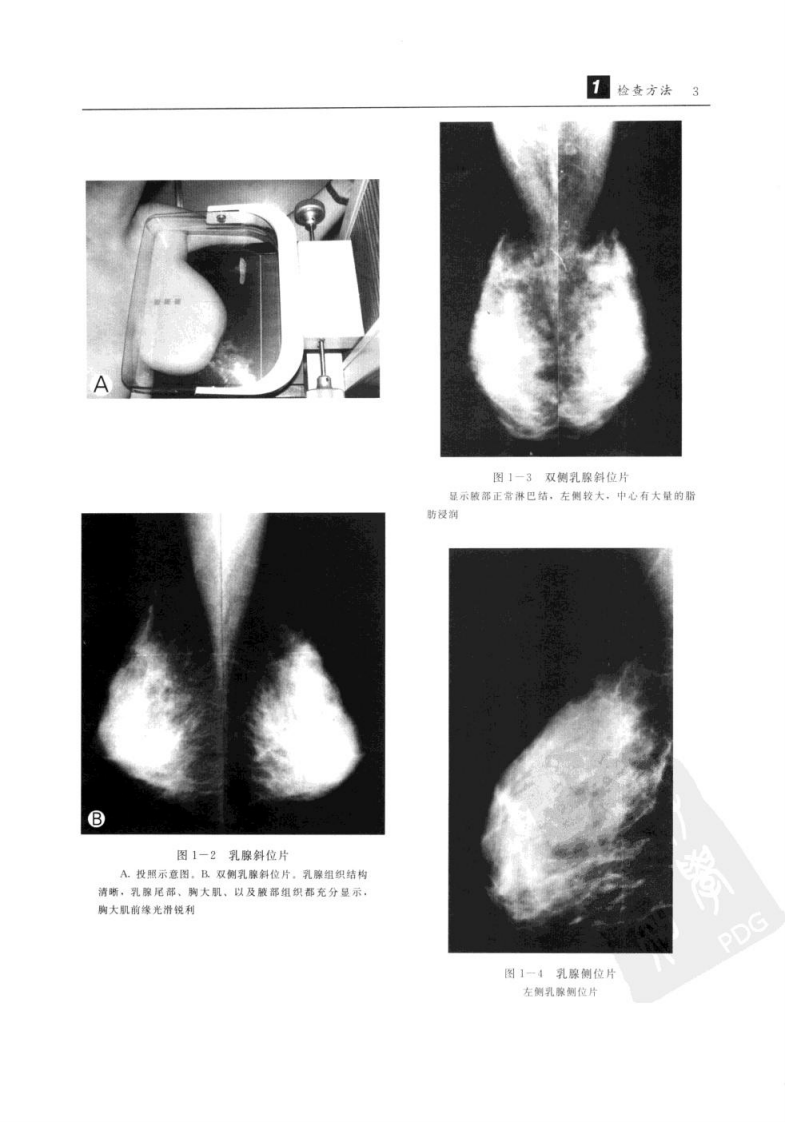

杜红文,张蕴主编.+乳腺疾病影像诊断学.+西安市:陕西科学技术出....pdf 第3页